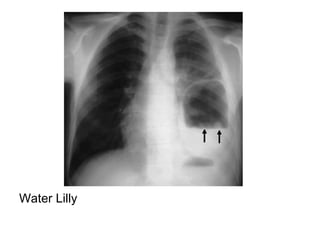

Air meniscus in the superior aspect of the lesion as a result of the enlarging

cyst communicating with an adjacent bronchiole

Water Lilly